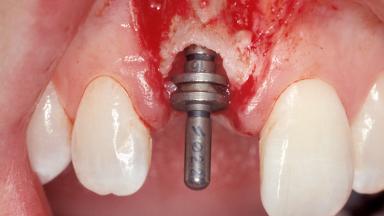

Immediate Placement of an Implant in a Maxillary Right Central Incisor Site

A 30-year-old female patient was referred to the office for the treatment of tooth 11. Her chief concern at the initial visit was to inquire, “Why is my tooth pink?” Upon clinical examination, it was determined that tooth 11 had a previous history of trauma and that the clinical crown had become noticeably pink in color as a result of internal resorption. This diagnosis was confirmed radiographically, indicating a large radiolucency involving the central and distal portions of the clinical crown. It was determined that restoration of this tooth was not possible, and that extraction was indicated. The presence of a mid-line diastema, which the patient wanted to reproduce, directed the treatment plan for tooth replacement utilizing a dental implant.

Type of Implants One-Piece|Reduced-Diameter

Placement Protocol Immediate implant placement

Tooth Site Maxillary incisor or canine

Socket Morphology Single-root socket

Socket Integrity Sufficient, with intact bone walls

Bone Volume Sufficient, with intact walls